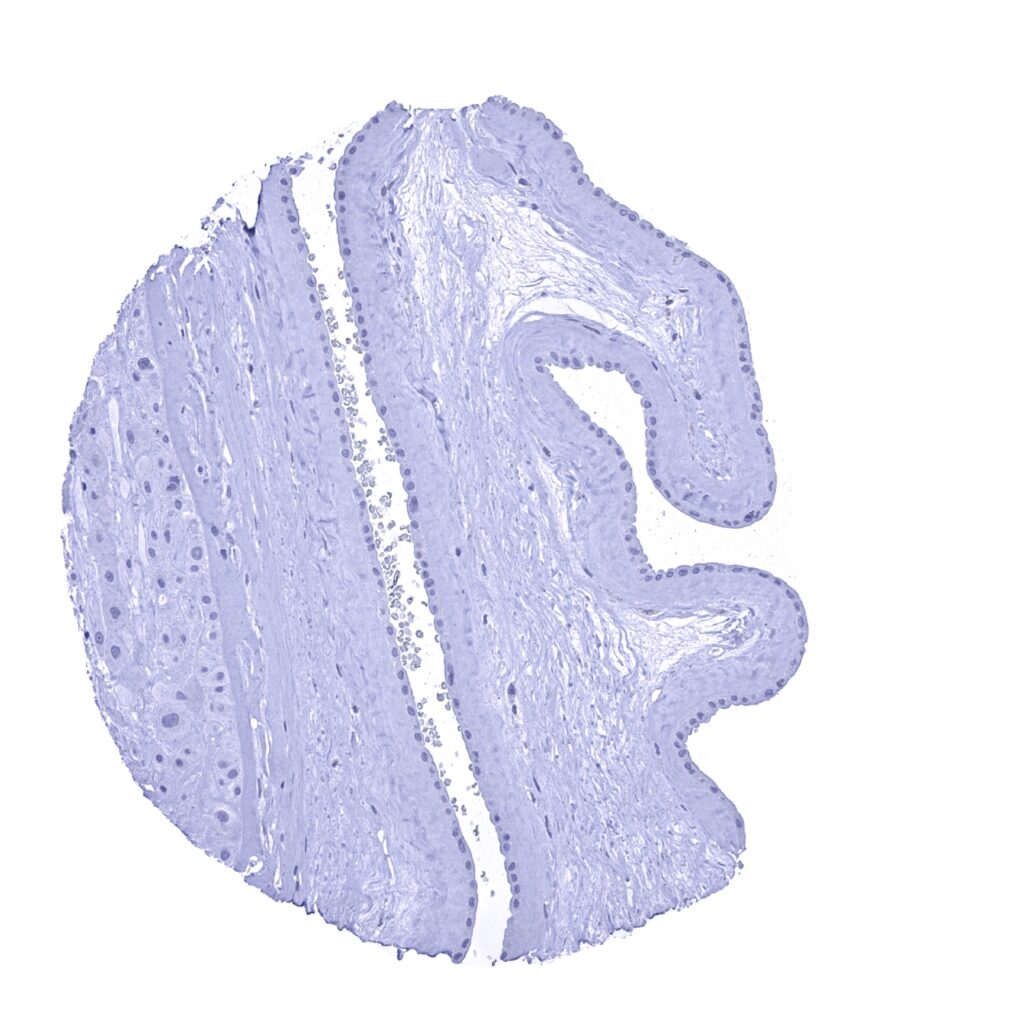

Urinary bladder, muscular wall